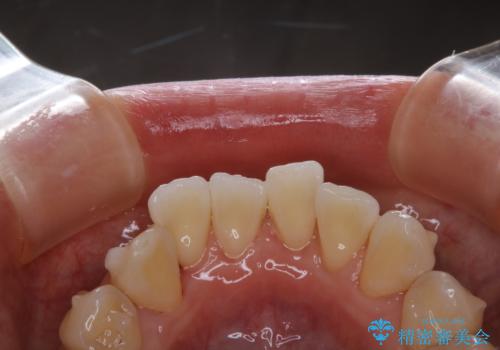

前歯の着色をPMTCできれいに